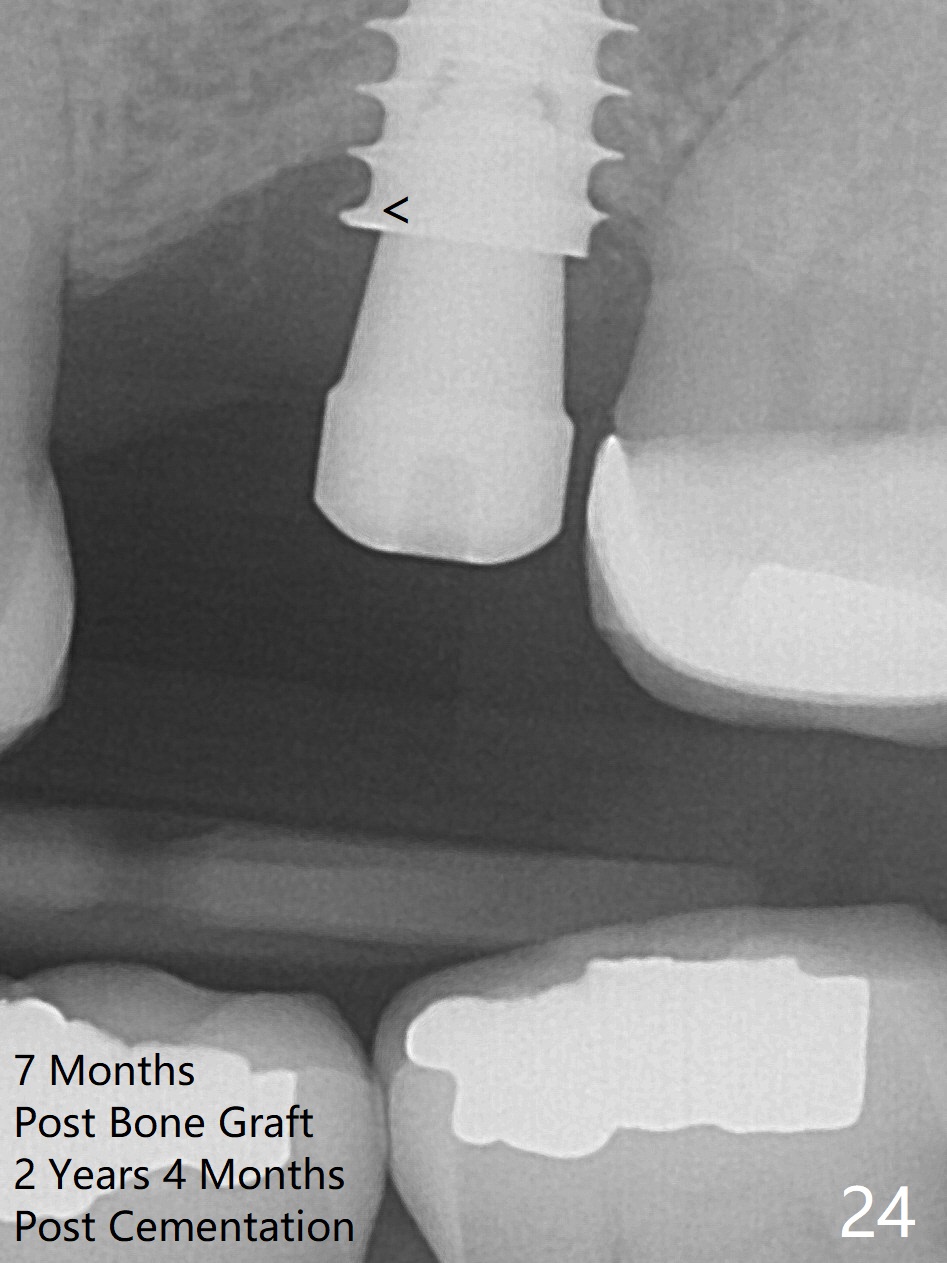

Bone volume and density seem to increase 4.5 and 10.5 months post cementation (Fig.20,21, as compared to Fig.15), although the buccal plate remains as concave as shown in Fig.18. A small healing abutment is placed because the implant is placed distal (Fig.24 (4.5x3 mm)). An angled abutment should be tried and #15 crown will be redone. Impression will be taken when the gingiva heals around the provisional crowns. Faint bone forms around the 1st implant thread (<; regraft may be unnecessary).